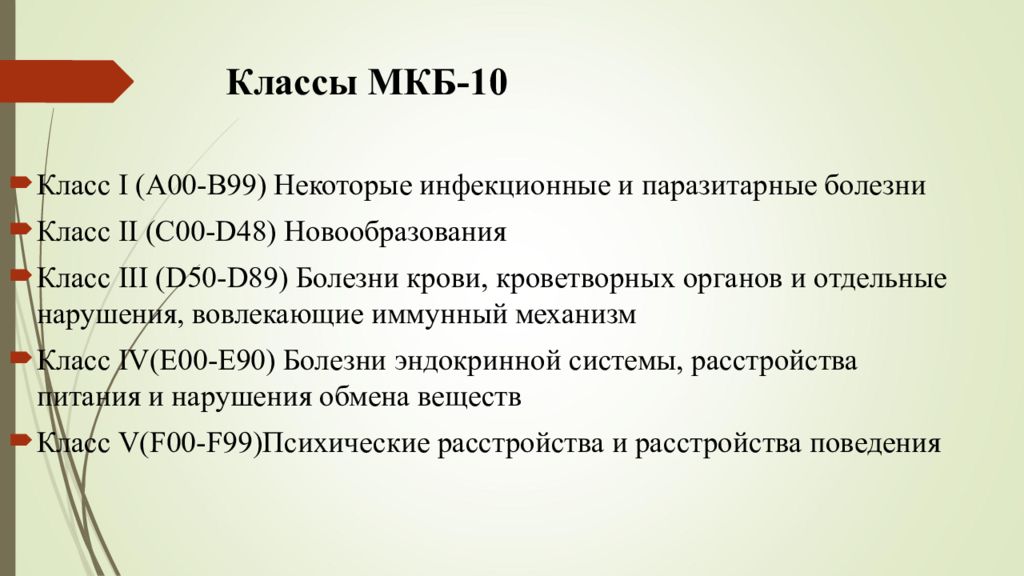

Острая внебольничная пневмония по МКБ-10: признаки и примеры